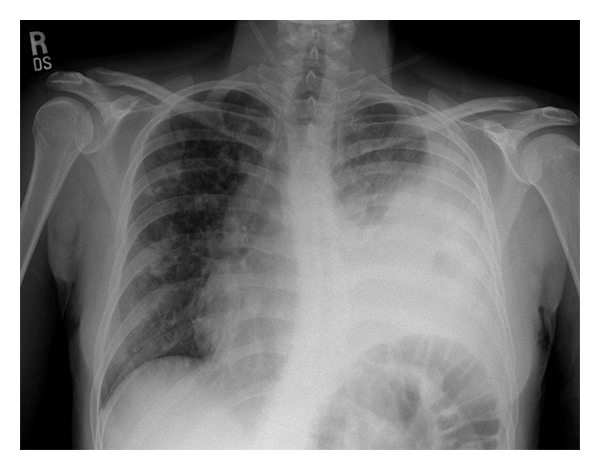

Input 3: What is seen in the X-ray and what should be done?

Image:

- Visual Med-Alpaca: Bilateral infiltrates and bilateral pleural effusion seen in a chest x-ray may indicate a respiratory infection or other respiratory conditions such as pneumonia pulmonary edema, or pleural effusion, it is important to consult a medical professional for a proper diagnosis and treatment plan.

OTHER METHODS

- VQA Medical Model: the decubitus

- Automatic Radiology Report Generation (Image-only): near complete opacification of the left hemi thorax with only a small amount of residual aerated lung in the left upper lobe .

- ChatGPT (GPT-3.5-Turbo) + Automatic Radiology Report Generation (Image-only): Opacification of the lung on an X-ray indicates that there is an abnormality in the lung tissue. In this case, the near-complete opacification of the left hemithorax with only a small amount of residual aerated lung in the left upper lobe suggests that there is likely a significant pathology present in the left lung. Possible causes of this finding include pneumonia, lung abscess, tumor or mass, or pleural effusion (fluid accumulation around the lung). It is important to determine the underlying cause of this finding as soon as possible. A follow-up diagnostic workup may include a CT scan of the chest, sputum culture, bronchoscopy, and/or a biopsy of any suspicious areas in the lung. The appropriate treatment will depend on the underlying cause, but it may include antibiotics, drainage of any fluid collections, or surgery to remove any masses or tumors. Prompt evaluation and treatment are necessary to prevent complications and improve outcomes.